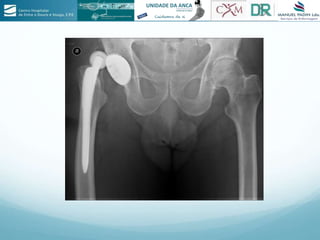

A técnica AMIS na prótese total da anca é descrita. A abordagem anterior de Hueter foi usada por 50 anos, mas depois desapareceu. A técnica AMIS foi desenvolvida por vários cirurgiões ortopédicos desde 1993 como uma alternativa minimamente invasiva à abordagem anterior tradicional.